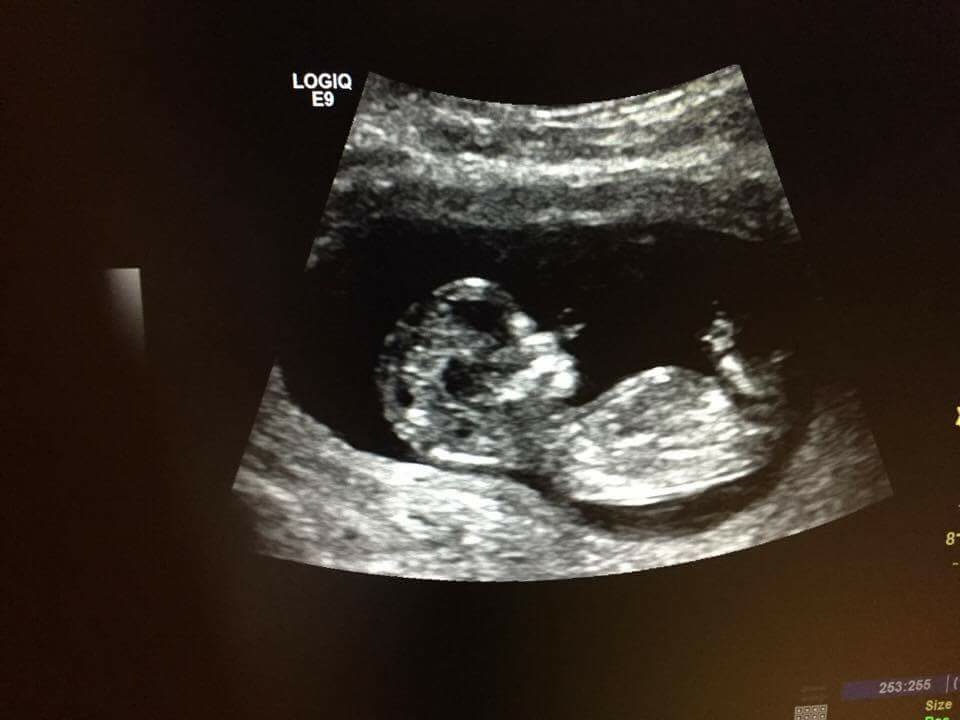

Gender??? 12Wks + 5days

Please help.. :confused:Boy or Girl?!

at the area i think you determine nub from.. i can see faint straight vertical white line... but behind that something faint also standing up/at an angle>?? any chance its a girl?!

only have this 1 picture atm

maybe girl but not a great pic

I think girl... holding thumbs for u...